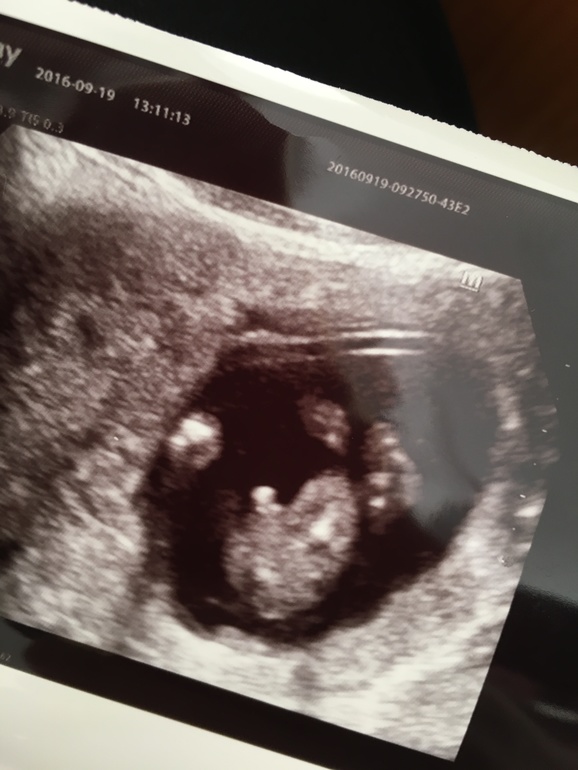

Узи в 12 недель ошиблось !) у нас будет второй сыночек 👼🏼👼🏼👼🏼💛

УЗИ, КТГ, доплерЗагремела я вчера в больничку с кровотечением . Низкая плацентация и гипертонус ( тут сделали второе УЗИ ) сын показал себя во всей красе )) и достоинство такое добротное😆Как говорит моя свекровь :" это на генном уровне "😂 В общем , видимо моя мечта , заплетать косички и покупать розовые платюшки так и останется мечтой )) ну ничего 😉Прорвёмся !))

Ой не знаю , не знаю 😜Мой дерётся со всеми , с братьями моими , которые старше, не представляю, что будет ,когда их будет двое . Надеюсь отец будет в силах их усмирить 😄 А вообще , я жду УЗИ в 20 недель , чтоб на 💯 % быть уверенной, что это мальчик ,а не пуповина между ног, т.к узистка сомневалась